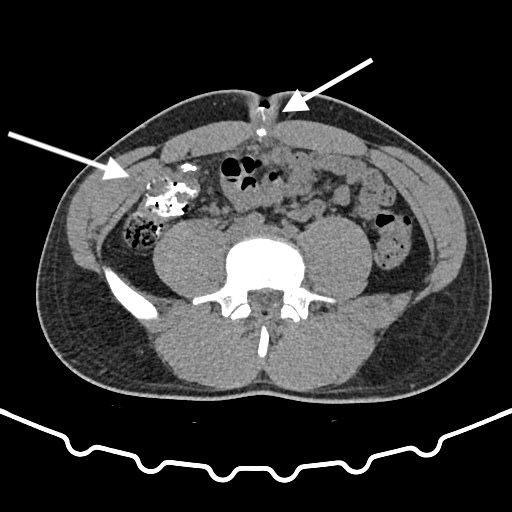

Three years after the appendectomy, the patient returned to the emergency department due to periumbilical pain and erythema that had persisted for three months. On further questioning the patient also reported intermittent diarrhea for one week, with no accompanying vomit or fever. During the physical examination, erythema and pain upon palpation of the umbilicus were observed. The blood tests showed no significant changes. Imaging with a CT scan and fistulogram through the umbilical granuloma allowed for the identification of a fistulous tract to a pericecal collection (figure 1-3). The patient was admitted and started on empiric antibiotic therapy with piperacillin and tazobactam.

Fig. 1-2: CT scan with fistulogram through the umbilical granuloma showing the fistulous tract to the cecum (white arrow) - axial view.